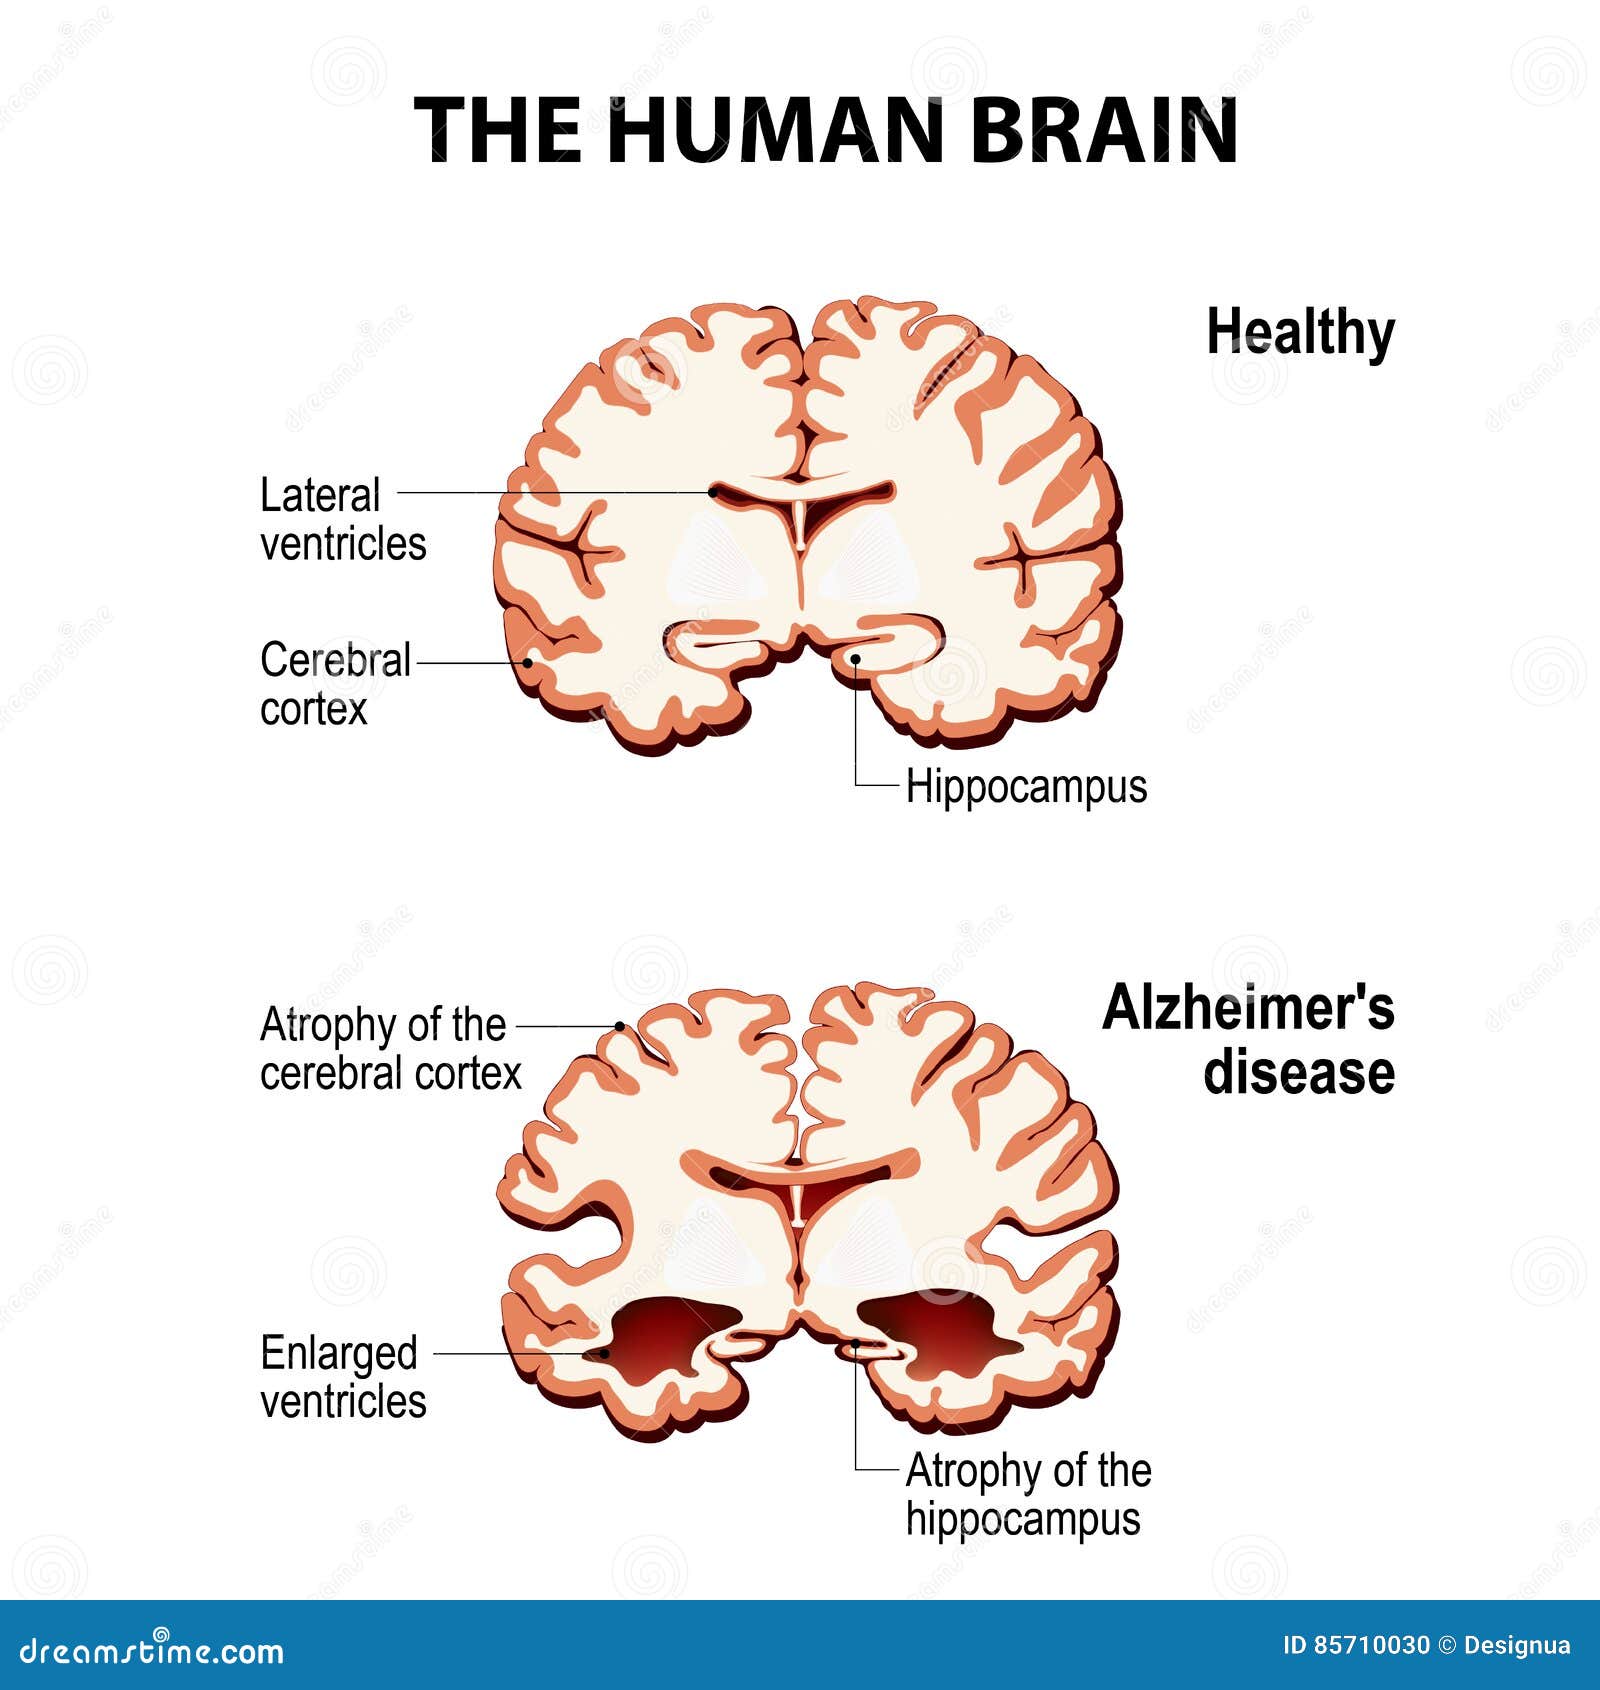

What Does The Brain Look Like With Dementia – DementiaTalkClub.com

The Healthy Brain (left) and the Alzheimer’s Brain (right) | Download …

Why Do Ventricles Enlarged In Alzheimer’s – DementiaTalkClub.com

Cross-section of the Human Brain with Alzheimer`s Disease Stock Vector …